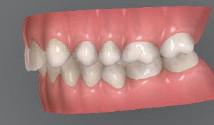

Цели на лечението и лечебен план Целите на лечението бяха следните: нивелиране и подреждане на зъбите и в двете зъбни дъги; отваряне на пространство за липсващия латерален резец; коригиране на отношенията при канините и моларите до клас I; и корекция на отклонението на срединната линия. Лечебният план включваше: корекция на отношенията при кучешките зъби и мола рите до клас I с дистализира не на максилата; отваряне на пространство в областта на #22 за поставя не на единичен имплант; корекция на срединната ли ния; и създаване на място за раз ширяване на зъб #12 и апрок симална редукция в долната челюст с цел подобряване на несъответствието по Болтън и осигуряване на подобра оклузия. Изпълнение на лечебния план Този случай бе изпълнен със системата за алайнери Invisalign (Align Technology). Одобреният първоначален лечебен план предвиждаше 49 алайне ра с дистализиране на задни те горни зъби до клас I (прибли зително с около 3.5 мм; фиг. 5). За бъдещия имплант в областта на липсващия латерал бе планирано пространство от 6.5 мм, докато във фронталния сегмент на долната челюст бе предвидена апроксимална редук ция. В дясната страна бутон за ластици клас II бе поставен на зъб #47 вместо на зъб #46, за да не се увреди короната на импланта. Понеже пациентката жи вееше в чужбина,

следните казуси: недобра оклу зия в дисталните зони по вре ме на дистализирането на гор ната челюст и накланяне на зъб #21 (фиг. 7). Последното се дължи на липсата на компози тен атачмънт на този зъб, каквото не бе зададено в пър Фиг. 4 Телерентгенография и цефалометричен анализ преди началото на лечението. Фиг. 5a–e Одобреният първоначален лечебен план. Фиг. 6a–h Снимки по време на лечението, показващи нуждата от внасяне на някои корекции. Фиг. 4 Фиг. 5a Фиг. 5d Фиг. 6a Фиг. 6d Фиг. 6f Фиг. 6b Фиг. 6e Фиг. 6g Фиг. 6h Фиг. 6c Фиг. 5e Фиг. 5b Фиг. 5c

Dental Tribune Bulgarian Edition / октомври 2022 г.18 воначалния план. Тези пробле ми бяха адресирани чрез допъл нителна поръчка на алайнери с торк контрол и зададено екст рудиране на задните зъби с цел установяване на добри оклузал ни контакти в дисталните об ласти, като бяха предвидени и оптимизирани атачмънти с контрол над корените за корекция на ангулацията на макси ларните резци (фиг. 8). Резултати от лечението Панорамната рентгено графия след ортодонтското лечение показа благоприятна паралелна позиция на съседни те зъби, подходяща за поставя не на имплант в областта на #22, както и конвергенция на ко рените на зъби #44 и 45 (фиг. 9), но преценихме, че няма да от деляме допълнително лечебно време за коригирането ѝ поради факта, че пациентката бе мно го доволна от постигнатия до момента резултат. След при ключване на лечението бяха постигнати отлични взаимо отношения клас I при мола рите и канините, а срединни

ти и клас II ластици е устано вено, че осигурява достатъч на дистализация без промяна на лицевата височина.23 Както се видя от цефалометричния анализ, точно това бе постиг нато и в представения случай като се има предвид, че лице вата височина остана същата като първоначалната. Предвид леката тенденция към дистал Фиг. 8a–e Поръчаните допълнителни алайнери. Фиг. 9 Панорамна рентгенография след края на лечението. Фиг. 10a–c Странични (а и с) и фронтална интраорални снимки след края на ортодонтското лечение и поставянето на импланта (b). Зъб #12 все още не беше протезиран. Фиг. 11а и b Оклузални снимки след ортодонтското лечение. Фиг. 7a Фиг. 8a Фиг. 7d Фиг. 8d Фиг. 9 Фиг. 10a Фиг. 10b Фиг. 10c Фиг. 11bФиг. 11a Фиг. 7b Фиг. 8b Фиг. 7e Фиг. 8e Фиг. 7c Фиг. 8c Фиг. 7a–e Интраоралната ситуация по време на лечението. клиничен случай с алайнери